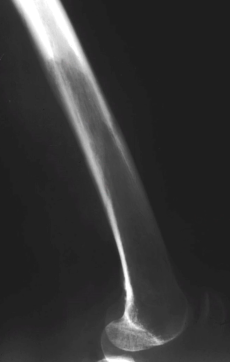

- Lyse des os longs en “brin d’herbe”

- Les lyses sont bien délimitées, avec une fin en “V”

Bowing

Fractures

- Fractures Complètes et incomplètes

- Banana Fractures